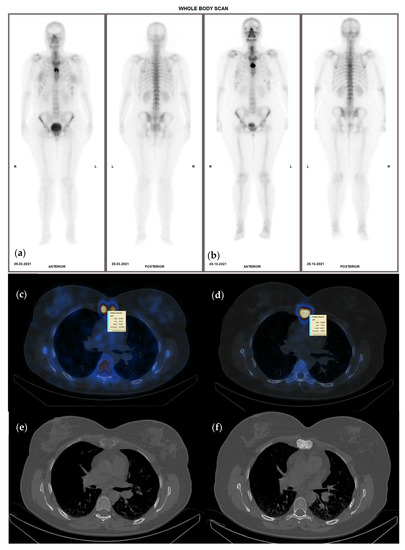

2.5. Follow-Up Diagnosis Criteria

- CR—no activity in any of the lesions on the follow up study;

- PR—more or equal to 30% decrease in summed SUVmax value;

- SD—neither PR nor PD (30% cut-off);

- PD—more than 30% increase of the summed SUVmax value or new tumor foci.

3.4. Interpretation of Quantitative SPECT-CT